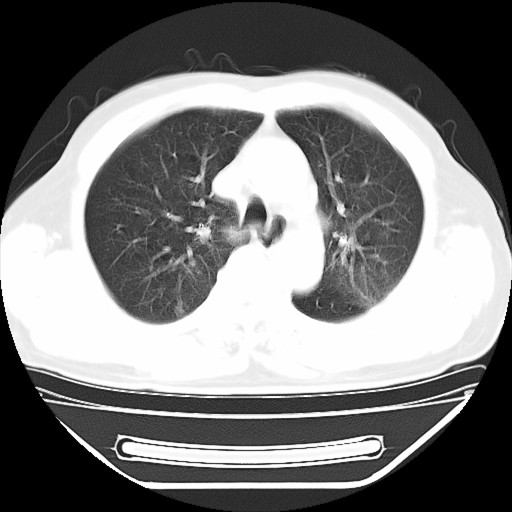

以下是引用hhcckk在2009-5-29 10:34:00的发言:[br]左下肺片絮状边缘模糊影,考虑感染,建议治疗后复查[br]